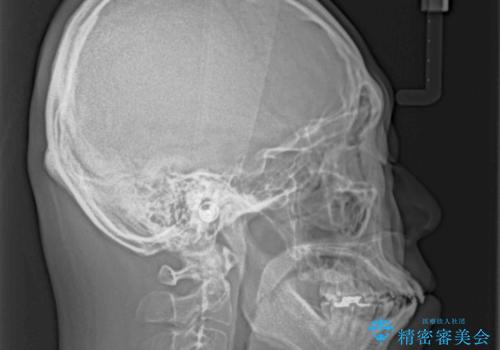

口が閉じられない 抜歯矯正で前歯の突出感を改善

- 口が閉じられないとのことで来院された患者様です。

顎先に力を入れないと唇が閉じきれない口元であったので、上下左右の第一小臼歯4本を抜歯して、ワイヤー装置にて矯正治療を行うこととしました。

2年から2年半の治療期間を想定しており、予定通りの期間で無事に終了することができました。

唇や顎先に力を入れないなくてもスムーズに唇を閉じることができるようになりました。